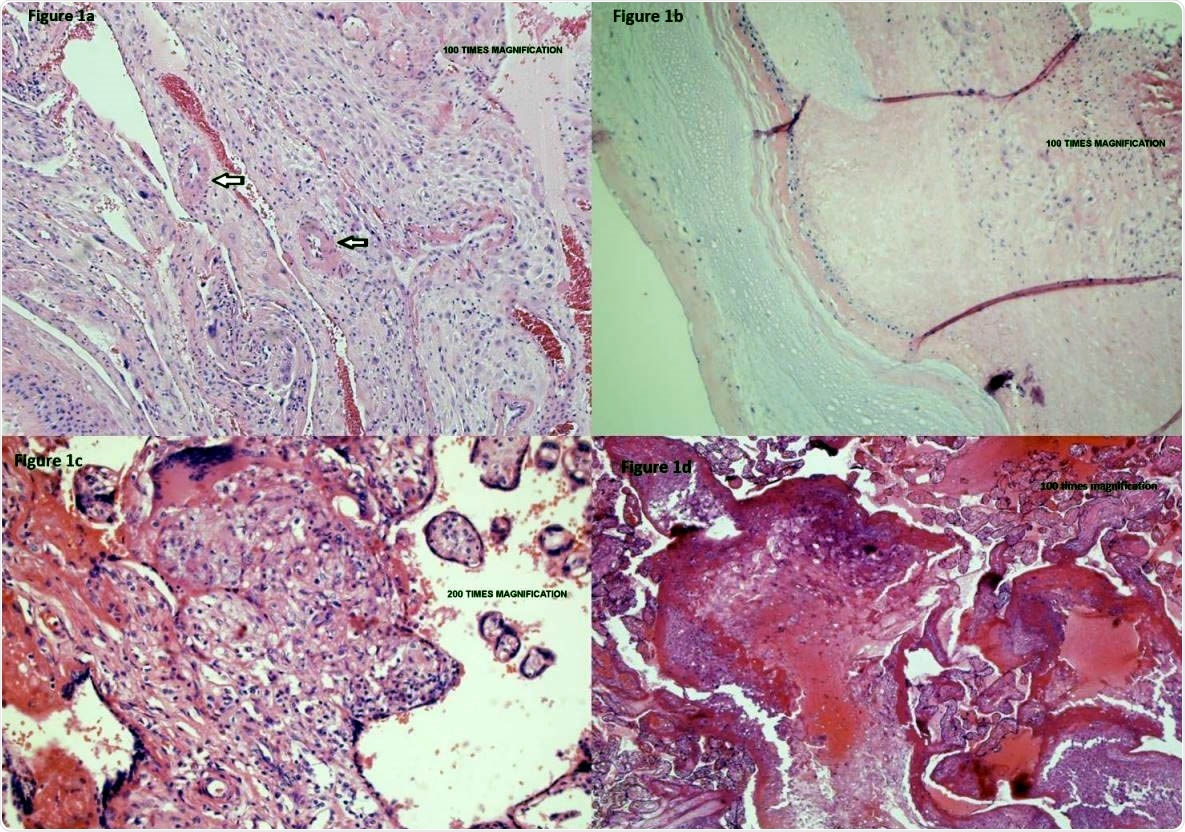

Placental vasculopathy in a pregnant woman with mild COVID-19 disease. Placental membranes showed decidua with scattered arterioles with thickened smooth muscle, consistent with hypertrophic arteriolopathy (vasculopathy) (Figure 1a – umbilical cord and placental membranes) and subchorionic laminar necrosis (Figure 1b – placental parenchyma under the umbilical cord). Placental disc showed focal areas of lympho-histiocytic inflammation consistent with chronic villitis (Figure 1c – central placental parenchyma) and scattered islands of extravillous trophoblasts (Figure 1d – peripheral placental parenchyma).

Histopathological examination of the placenta showed evidence of acute uterine hypoxia as shown by subchorionic laminar necrosis, with underlying chronic uterine hypoxia, shown by extravillous trophoblasts and focal chronic villitis. Immunohistochemistry (IHC) analysis showed the presence of SARS-CoV-2 antigens extensively distributed throughout the placenta. These were present under the umbilical cord, in both central and peripheral placenta, in the endothelial cells of the chorionic villi, and uncommonly within trophoblasts.